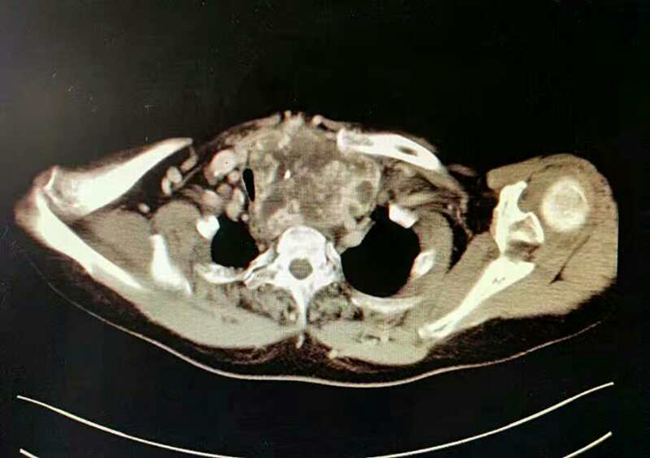

妇瘤病院,诊断为子宫内膜癌,同时发现患有巨大甲状腺肿瘤并深入胸骨后方,气管严重受压变窄,最窄处仅5毫米。若直接行妇科手术,全麻插管困难,且可能出现术后窒息等严重并发症危及生命。不行手术则其妇科疾病难以有效治疗,患者十分着急。素股

妇瘤病院赵西侠主任与头颈肿瘤外科梁秦龙主任医师共同会诊后分析,该患者甲状腺巨大肿瘤,深入胸骨后方,气管严重受压变形,且肿瘤与纵膈大血管分解不清楚,手术风险很大。但是如果不先行甲状腺手术,不跨越这个难关,子宫内膜癌手术时无法进行的。所以与家属沟通后先行甲状腺手术。为确保手术万无一失,头颈肿瘤外科赵华、梁秦龙主任团队做了充分的术前准备,并制定详细手术方案。11月16日,在麻醉科陈军主任团队大力协助下,由梁秦龙主任医师主刀,历时1个多小时,成功为患者切除胸骨后巨大甲状腺肿瘤(大小:12cm*10cm*8cm),手术顺利,术后患者恢复良好,第二天即可下床活动,自感呼吸明显通畅,现已转回妇瘤病院进行后续治疗。